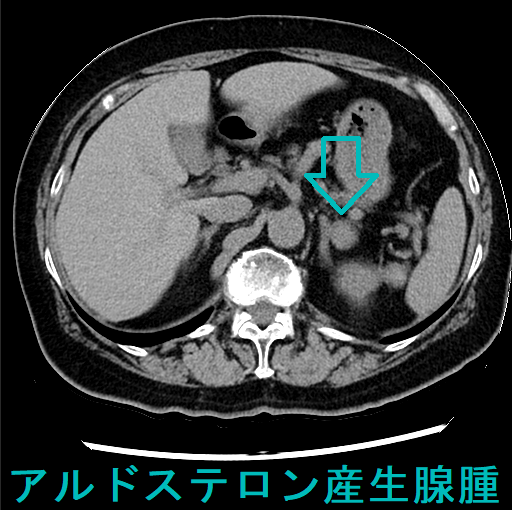

2cm以下の小さいものがほとんどで、超音波検査やCTで見つかりにくい難点があります。両側過形成腺腫・非機能性腺腫の合併が多いです。

副腎腫瘍による原発性アルドステロン症は高血圧の15%だが本態性高血圧と間違えられ治療されている。心血管障害が多く予後不良。超音波検査やCTで見つかりにくい、普通の降圧薬が効きにくい、血圧変動激しい、ノンディパー型、低カリウム血症(カリウム正常の方が多い)で筋力低下、脱力発作、不整脈、腎性尿崩症、血圧下がってもアルドステロンそのもので動脈硬化が進行し脳卒中・心筋梗塞・心房細動。血漿アルドステロン濃度/血漿レニン活性比、カプトプリル負荷試験などで診断。治療は腹腔鏡下手術、スピロノラクトン(アルダクトンA)・エプレレノン(セララ)・エサキセレノン(ミネブロ)。